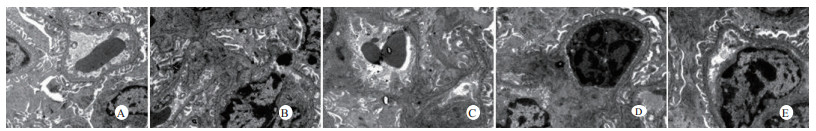

光镜下可见,假手术组肺泡大小形态均匀,结构清晰,肺泡腔内无出血和白细胞浸润;感染性休克组肺泡壁破坏严重,血管壁和肺泡间隔明显增厚;U50488H+感染性休克组大部分肺泡腔均匀一致,肺间隔略增厚,肺泡壁轻度水肿,但出血和白细胞浸润情况比感染性休克组明显减轻(图 1)。假手术组心肌细胞大小一致,排列整齐,核浆比正常,心肌细胞核呈椭圆型,胞浆均匀红染;感染性休克组心肌细胞肿胀,体积明显增大,细胞核大而异型,核内染色质固缩、边集,白细胞浸润明显增加;U50488H+感染性休克组多数心肌细胞形态相对正常,少数心肌细胞呈现脂肪变性(图 2)。假手术组肝细胞结构完整,肝小叶形态正常;感染性休克组肝细胞显著肿胀、呈空泡样和点状/小片状坏死;U50488H+感染性休克组肝细胞轻度肿胀,未见明显坏死灶、肝血窦扩张和炎性细胞浸润(图 3)。假手术组肾组织结构大致正常;感染性休克组肾小管细胞轻度水肿、空泡变性;U50488H+感染性休克组肾小管形态大致正常,间质无明显出血水肿(图 4)。

| A:假手术组,B:感染性休克组,C:U50488H+感染性休克组,D:nor-BNI+U50488H+感染性休克组,E:nor-BNI+感染性休克组 图 3 各组光镜下肝组织病理学改变(HE×400) Fig 3 Histopathological features of liver(HE×400) |

扫描电镜下可见,假手术组肺泡形态完整,肺泡壁光滑;感染性休克组肺泡明显压缩畸形,肺泡隔肿胀、扭曲、隆起;U50488H+感染性休克组肺泡形态大致完整,少数肺泡壁肿胀受损(图 5)。透射电镜下可见,假手术组心肌细胞形态正常;感染性休克组心肌细胞溶解、坏死、肌纤维断裂;U50488H+感染性休克组心肌细胞大致正常,无明显坏死(图 6)。假手术组肝细胞形态正常,毛细胆管未见扩张;感染性休克组肝细胞大片坏死,毛细胆管明显扩张;U50488H+感染性休克组肝细胞形态大致正常,毛细胆管略扩张(图 7)。假手术组肾小管上皮细胞形态狭长,核卵圆形,位于基底部;感染性休克组肾小管上皮断裂,微绒毛缺失;U50488H+感染性休克组肾小管上皮细胞大致正常,微绒毛不平滑,但无明显坏死(图 8)。

| A:假手术组,B:感染性休克组,C:U50488H+感染性休克组,D:nor-BNI+U50488H+感染性休克组,E:nor-BNI+感染性休克组 图 7 肝细胞透射电镜检查(×10 000) Fig 7 Transmission electronic microscopic photos of liver(×10 000) |